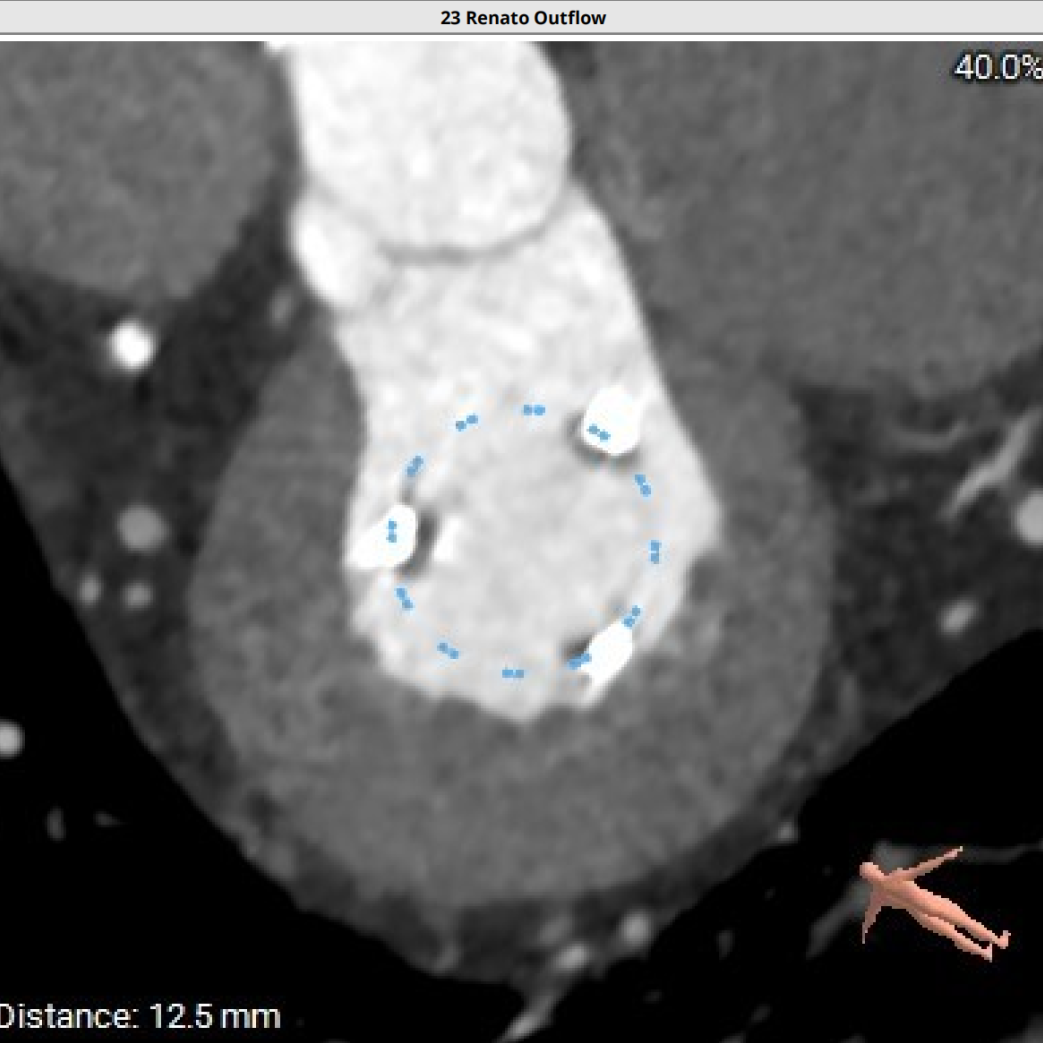

模拟25#Renatus植入

NEO-LVOT面积293.6mm²,新流出道梗阻风险低